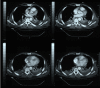

Background: We report a case of delayed endovascular correction of graft collapse occurred after emergent Thoracic Endovascular Aortic Repair (TEVAR) for traumatic aortic isthmus rupture.

Case presentation: In 7th post-operative day after emergent TEVAR for traumatic aortic isthmus rupture (Gore TAG® 28-150), a partial collapse of the endoprosthesis at the descending tract occurred, with no signs of visceral ischemia. Considering patient's clinical conditions, the graft collapse wasn't treated at that time. When general conditions allowed reintervention, the patient refused any new treatment, so he was discharged.Four months later the patient complained of severe gluteal and sural claudication, erectile disfunction and abdominal angina; endovascular correction was performed. At 18 months the graft was still patent.